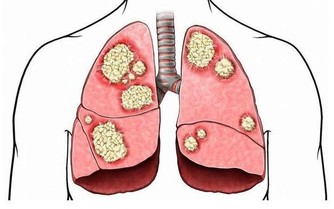

痰毒有的人早上起來不停吐痰,沒完沒了,這就說明有痰毒了。痰毒一般由飲食而來,或因肺功能不好導致。如果氣管不好,痰多,可以喝二陳湯來治癒,一服藥茯苓、法半夏、陳皮各10克,甘草6克,用水煮了喝,喝上7天痰即可化。日常飲食上,蘿蔔是最好的化痰食物,可以買生蘿蔔加點香醋涼拌吃;另外還可以多吃冬瓜、無花果、紫菜、羅漢果等清熱化痰之品。